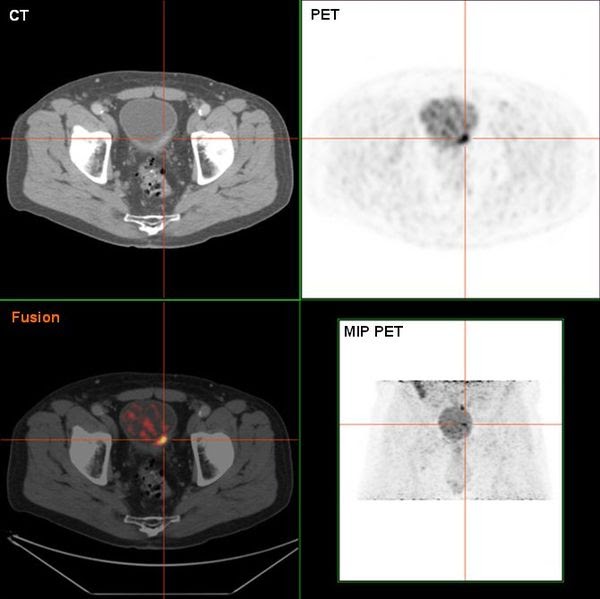

Imaging modalities for improved bladder tumor detection. Papillary and …

Imaging modalities for improved bladder tumor detection. Papillary and …

mpMRI of a male patient with stage T1 high-grade bladder cancer 3 …